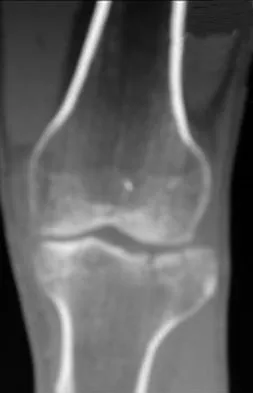

An 8-year-old girl was treated for a Salter-Harris type I fracture of the right distal femur 2 years ago. Examination reveals symmetric knee flexion, extension, and frontal alignment compared to the contralateral knee. She has 1-cm of shortening of the right femur. History reveals that she has always been in the 50th percentile for height, and her skeletal age matches her chronologic age. Radiographs are shown in Figure 9. What is the expected consequence at maturity?

Explanation

The child has a near complete central physeal arrest of the distal femur and worsening limb-length discrepancy will develop. She is growing at the average rate for the population. The distal femoral physis grows at a rate of roughly 9 mm per year. Girls finish their growth at approximately age 14 years. Thus, at maturity the left leg will be 6.4 cm longer than the right. An angular deformity has not developed at this point and her arrest is central; therefore, angular deformity is unlikely to develop in any plane. Little DG, Nigo L, Aiona MD: Deficiencies of current methods for the timing of epiphysiodesis. J Pediatr Orthop 1996;16:173-179.